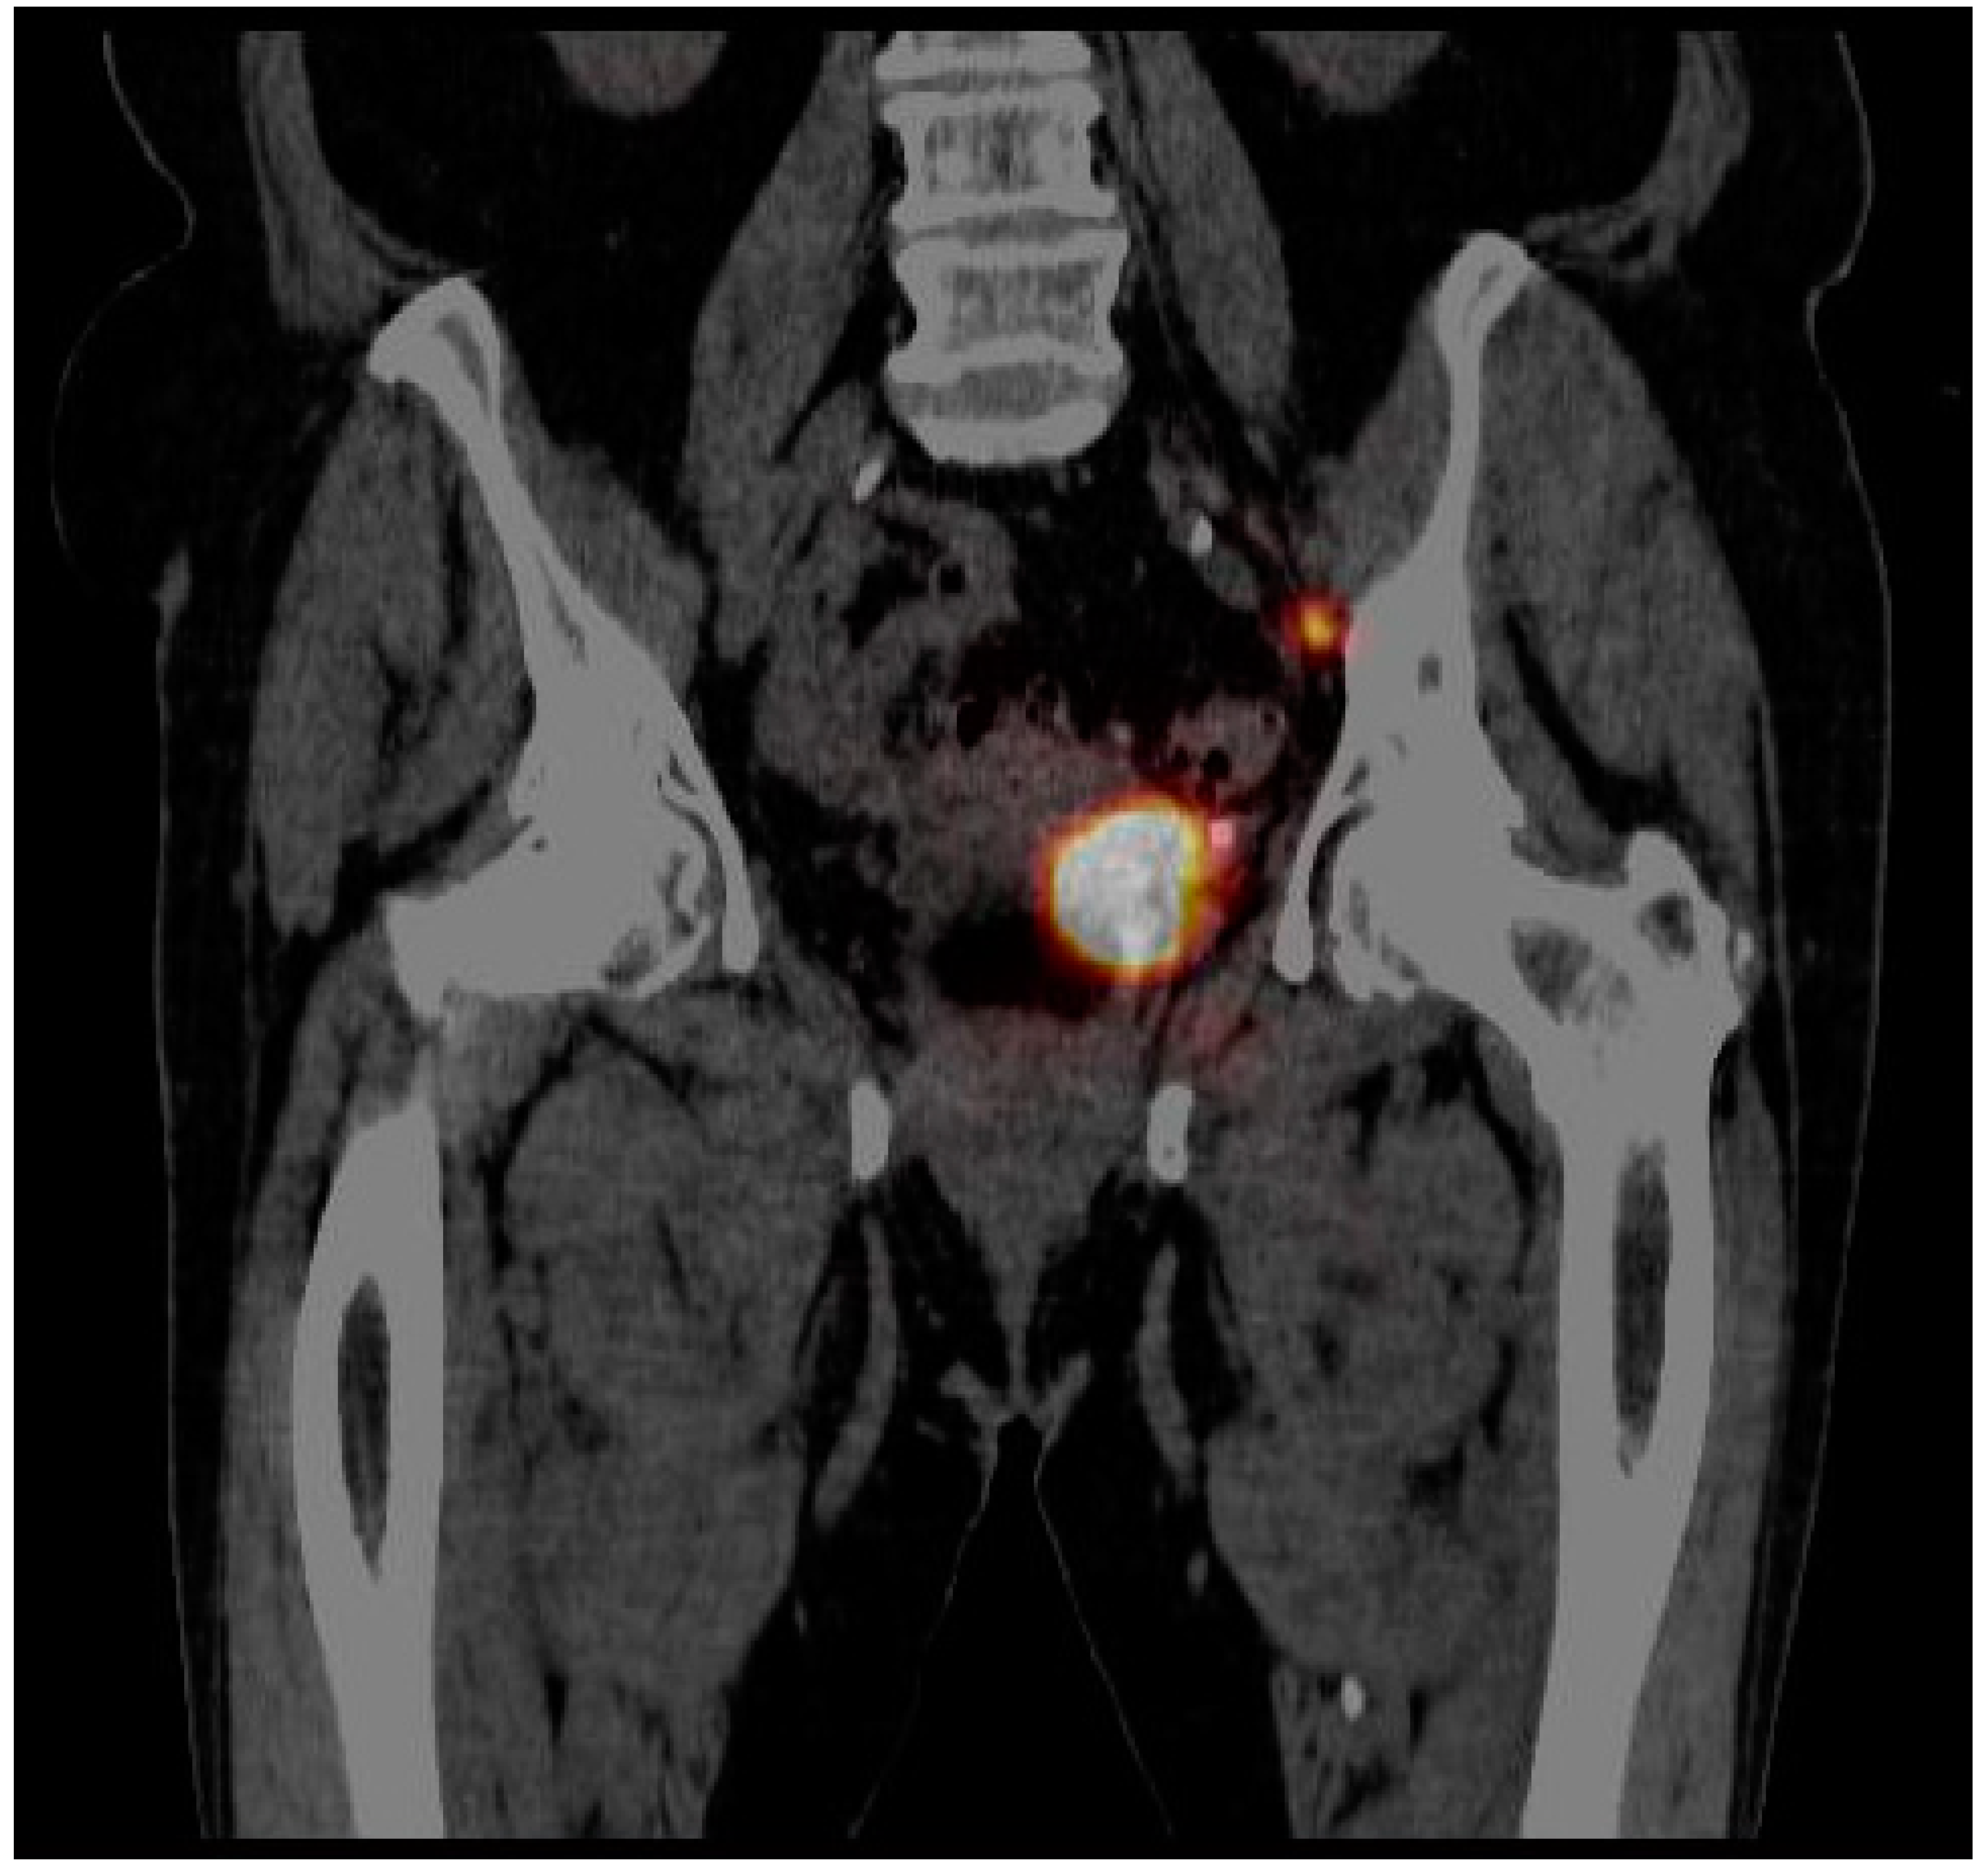

| Lymphatic outflow analysis | |

| Number of patients with identified SLNs | 2 (10.5%) |

| Number of patients with no lymphatic outflow | 17 (89.5%) |

| Number of identified SLNs | 2 (10.5%) |